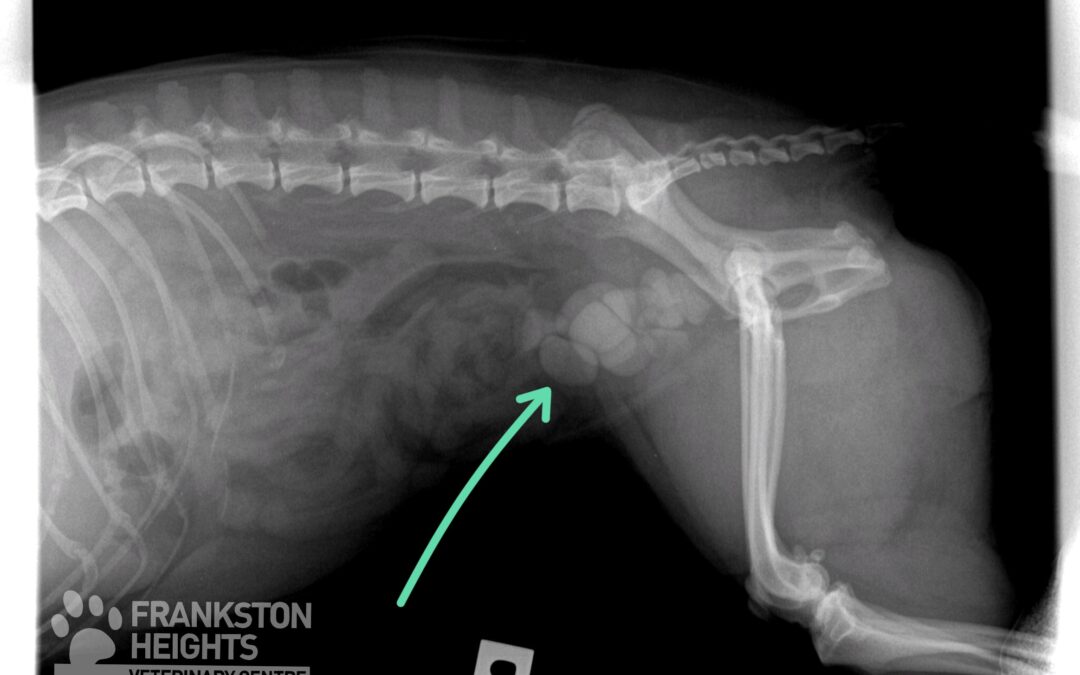

Tilly_xray

May 24, 2019